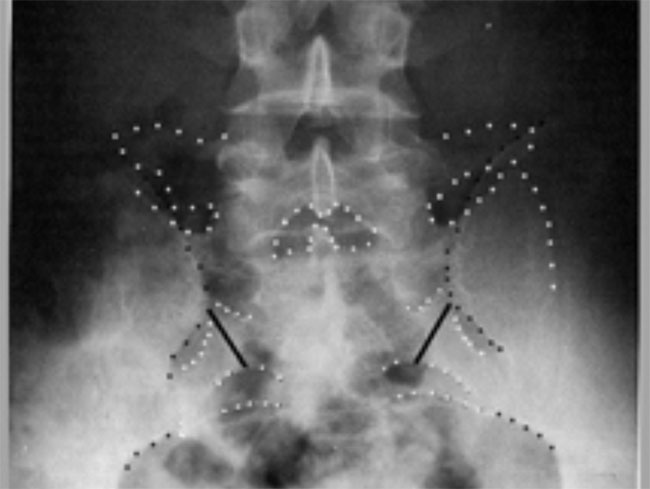

Roentgenograms taken before (Above) and after (Below) correction

of SIJD reveal a dysfunction of

the innominate bone cephalad and laterally on the sacrum. Note movement

of the PSISs relative to

the sacral foramina.